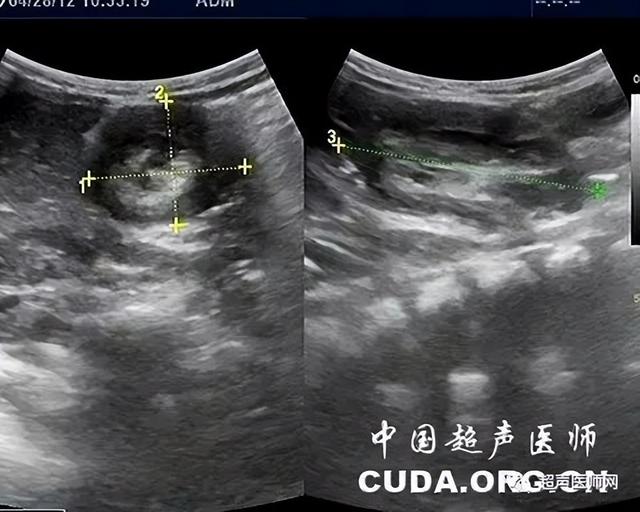

肠套叠超声图片

【规培笔记】再谈肠套叠